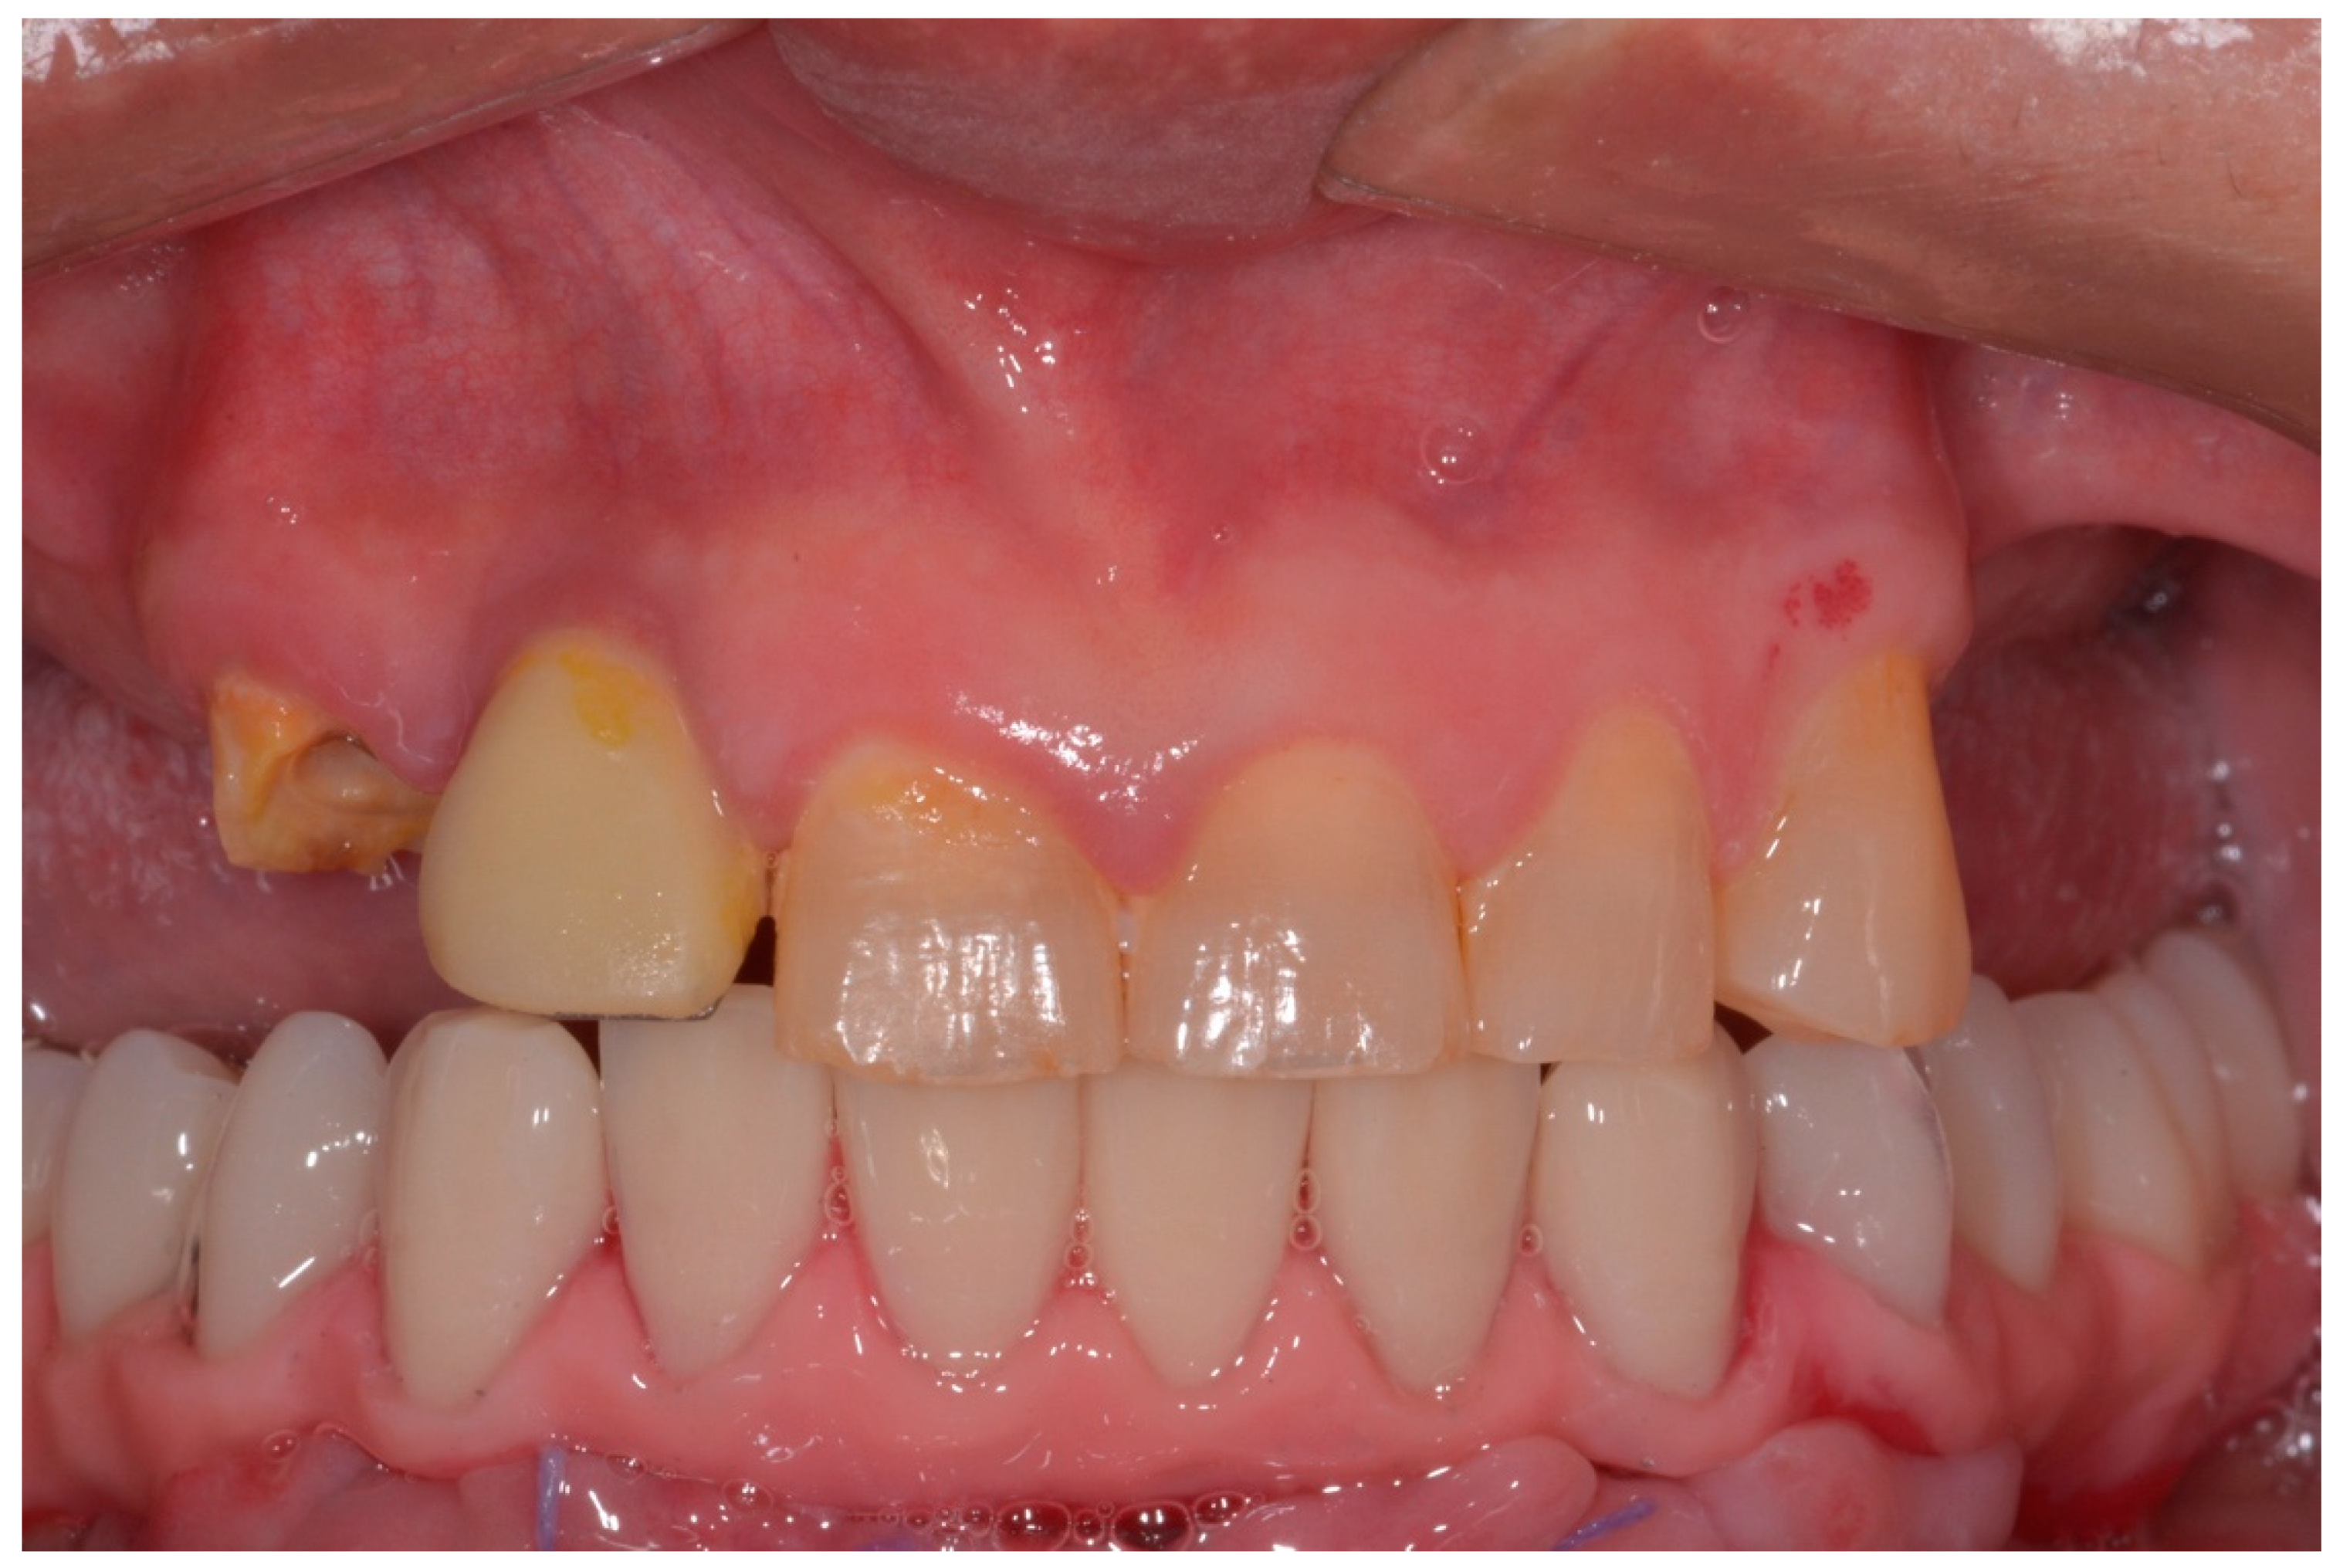

All patients received implants with a grit-blasted and acid-etched surface (Ossean®; Intra-Lock International®, Inc., Boca Raton, FL, USA) that were placed using a sterile surgical technique, as recommended by the manufacturer. Maximum care was taken to place the implants, regardless of whether they were inserted in an edentulous ridge or an extraction site, with a minimum insertion torque of 35 Ncm and not exceeding 50 Ncm (Figure 3).

The peri-implant bone defects in the extraction sockets were grafted with a cortico-cancellous porcine bone (GTO, Tecnoss-Dental, Giaveno, Italy). Flat abutments (FlatOne®; Intra-Lock International®, Inc., Boca Raton, FL, USA) were then connected to the implants, and the flap was sutured (Figure 4).

Figure 3. Implants were inserted, and flat abutment connected.

Figure 4. Flat abutment connection.